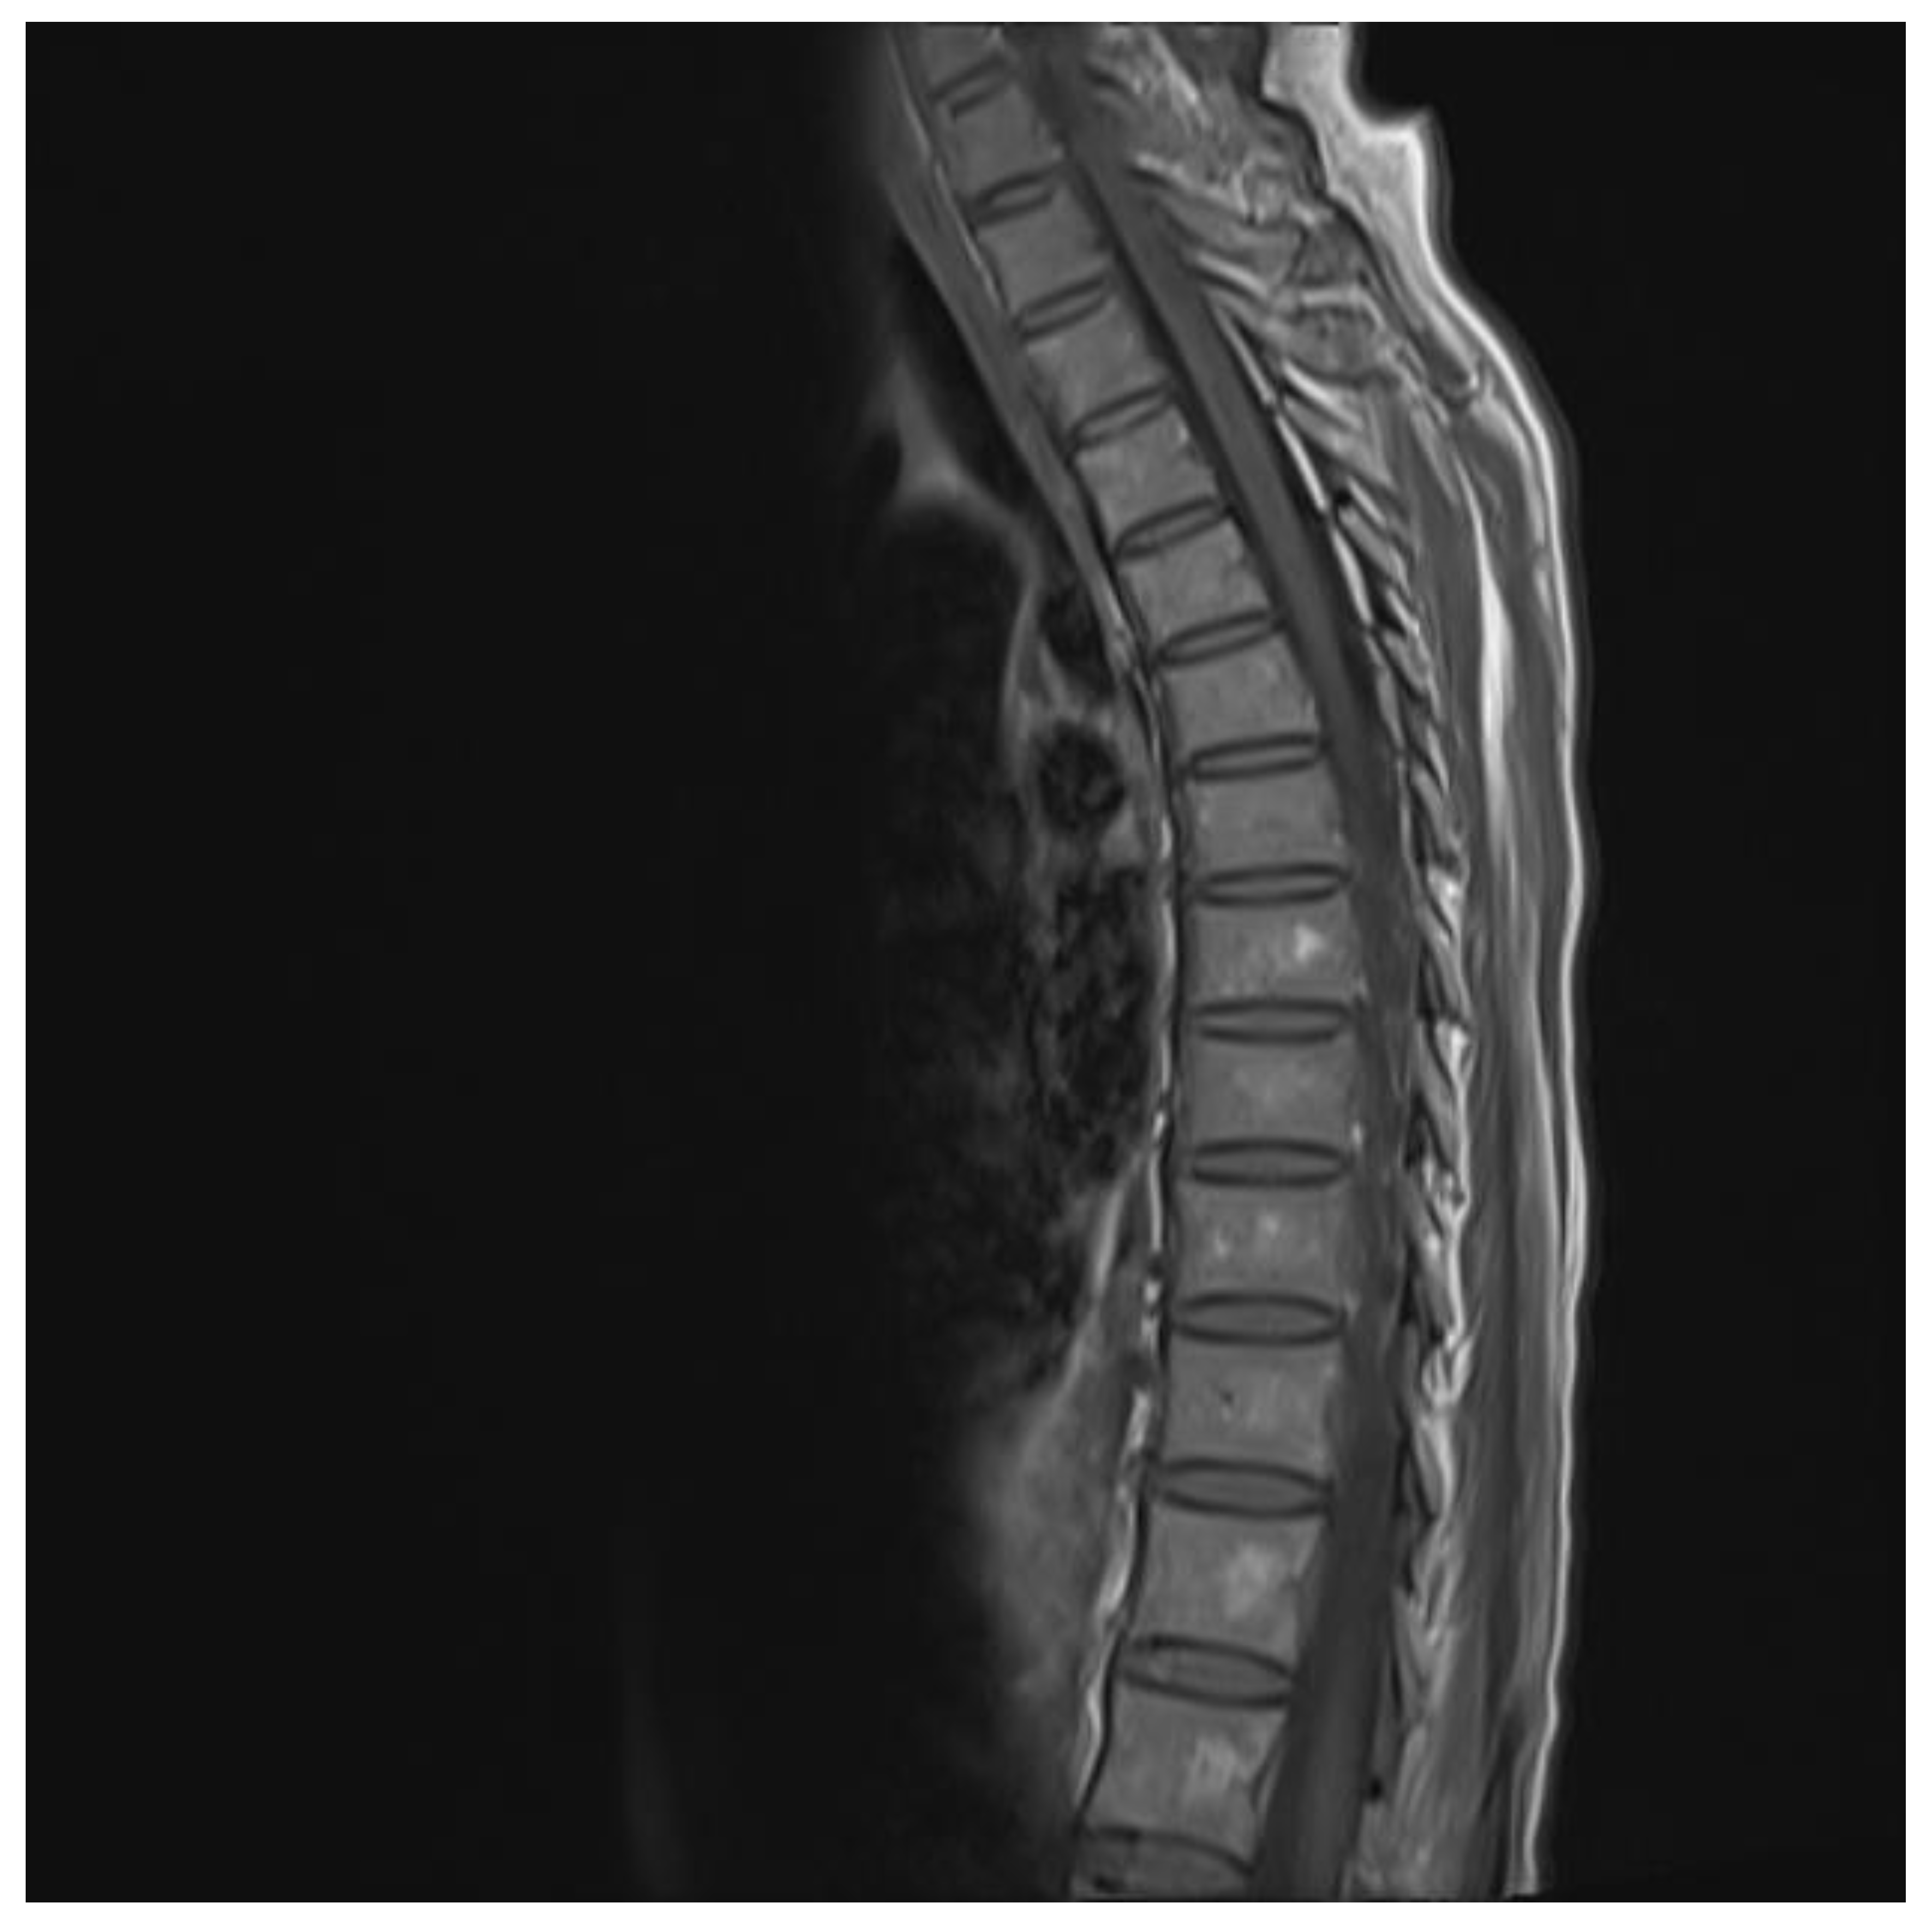

The chest and brain tomography did not display any abnormalities. The spinal MRI performed on the second day of hospital admission showed irregular intramedullary signal enhancement on the T2 sequence with diffuse lesions ranging from the sixth cervical vertebra to the seventh dorsal vertebral (Figure 1). The T1 sequence showed the spinal cord with multiple hypointense lesions centrally located at the cervical–dorsal level (Figure 2), while the transversal image T2-weighted image of the spinal cord showed hyperintense lesions in the white matter and in the posterior portion of the spinal cord (Figure 3).

Figure 2.

T1 image showing hypodense lesion in the cervical and thoracic cord.

MRI has an important role in the diagnosis and classification of TM, as it allows us to identify hyperintense spinal cord injury in T2-weighted images, and when it affects at least three vertebral segments in the sagittal slices, TM is classified as LETM [3]. T2- weighted MRI demonstrated an intramedullary increased signal in the central portion of the spinal cord as the most common finding [5]. MRI images in immunocompetent patients with TM show that the cervicothoracic cord is affected more frequently, as in our case, unlike immunosuppressed patients, in which tropism has been seen in the cauda equina or the conus medullaris [13]. The aforementioned findings coincide with the RMI in the case report presented, in which hyperintense cervicothoracic spinal cord involvement was observed in the T2-weighted image. This was specifically seen in patients with NMO (anti-AQP4 Ab) associated with patients with SLE and Sjögren’s disease [3,14]; while there is evidence of markedly hyperintense foci on T2 described as “Bright Spotty Lesions”, characteristic for NMO, in this case, anti-AQP4 antibody sera were not performed. However, the results of the IgM serological test for cytomegalovirus was positive, which confirmed the acute installation of the infectious image.